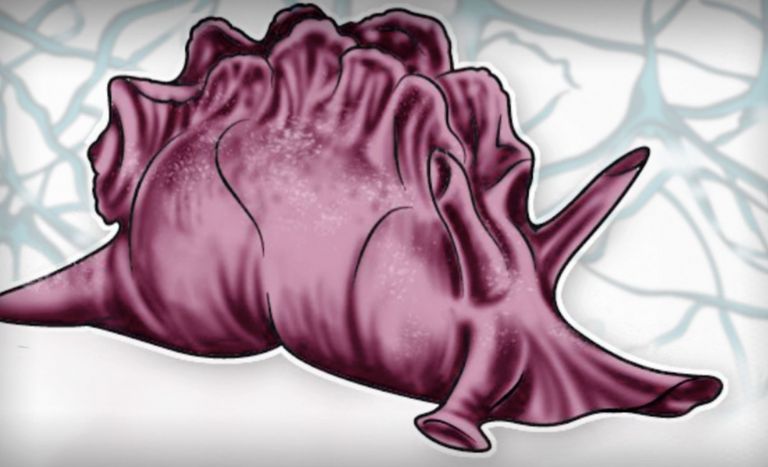

Offenbar hatte Karl Lashley bei seinen Studien am falschen Ort gesucht. In seinen Rattenexperimenten hatte er stets Teile der Hirnrinde, also der äußersten Schicht des Gehirns entfernt. Dieses Hirnareal ist in der Entwicklungsgeschichte des Gehirns das jüngste, alle anderen hielt Lashley für zu primitiv. H.M. fehlte es aber nicht an Hirnrinde, Scoville hatte einen Teil des Mandelkerns, der Amygdala, entfernt und fast den gesamten Hippocampus. Diese Region an der Innenseite der Schläfenlappen war offenbar entscheidend für das Formen neuer Erinnerungen.

Aber H.M. hat nicht nur gezeigt, wie bedeutend der Hippocampus ist. Der Fall machte auch deutlich, dass das Gedächtnis aus verschiedenen Modulen besteht. In einem berühmten Experiment gab Brenda Milner H.M. eine Geschicklichkeitsaufgabe. Zwischen zwei ineinander geschachtelten Sternen sollte er den Umriss eines dritten Sterns zeichnen, durfte seine Hand und das Papier dabei aber nur in einem Spiegel beobachten. Obwohl H.M. sich nie daran erinnern konnte, diese Aufgabe schon einmal geübt zu haben, wurde er von Mal zu Mal besser. Einmal sagte er sogar erstaunt, er habe sich die Aufgabe schwerer vorgestellt.

Manchmal überraschte H.M. die Forscher mit anderen Erinnerungen, etwa wichtiger Persönlichkeiten, die erst nach seiner Operation berühmt wurden. So konnte er auf Nachfrage den Initialen JFK den Namen John F. Kennedy zuordnen – und wusste, dass er 1963 ermordet wurde. Und „Bob Dy…“ konnte er zu „Bob Dylan“ vervollständigen, obwohl der Musiker erst in den 60ern bekannt wurde. H.M. dürfte einer der am besten untersuchten Menschen aller Zeiten sein und trotzdem ist bis heute unklar, woher diese Erinnerungen kamen. „Die Tatsache, dass er sich überhaupt irgendetwas merken kann, reicht aus, um einen Wissenschaftler völlig umzuhauen“, sagt die Neurowissenschaftlerin Suzanne Corkin vom Massachusetts Institute of Technology, die von 1962 an bis kurz vor seinem Tod mit ihm arbeitete. Damit zeigte sich eindrucksvoll, dass das Gedächtnis aus verschiedenen Modulen besteht, die an unterschiedlichen Orten im Gehirn abgespeichert werden.